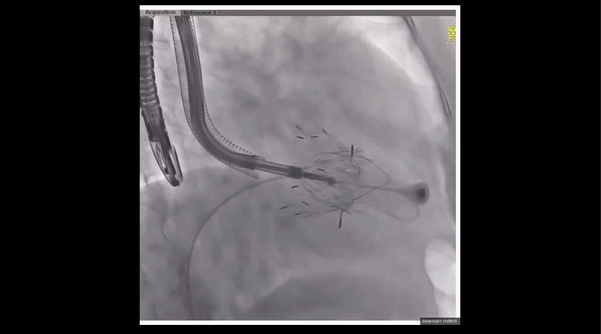

術(shù)中經(jīng)食道超聲輔助下可見LuX-Valve Plus夾持件抓捕瓣葉狀態(tài)良好,夾持件在位,室間隔錨定位置良好,假體瓣膜整體錨定狀態(tài)穩(wěn)固。

術(shù)后即刻經(jīng)食道超聲可見,三尖瓣假體瓣膜位置合適,牛心包瓣葉運(yùn)動狀態(tài)良好,開閉正常,瓣周及瓣葉對合緣處未見明顯返流,心電圖及心包狀態(tài)較術(shù)前無明顯變化。

瓣膜釋放